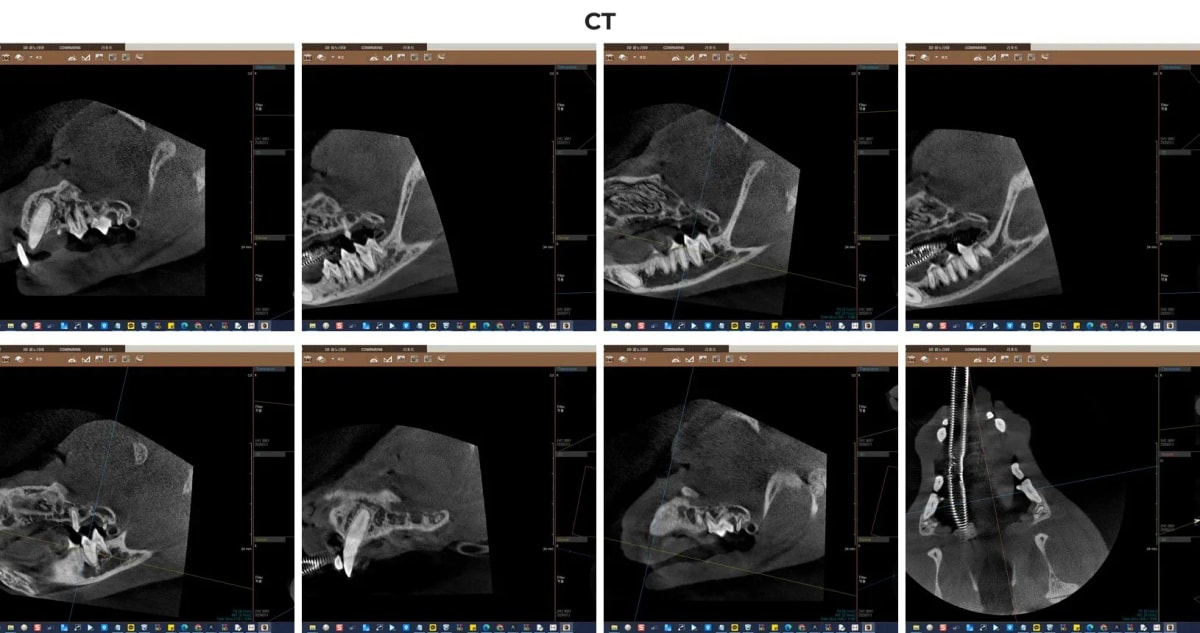

2. 정밀 진단의 첫걸음, 치과 전용 CT 촬영

일반 구강 방사선만으로는 치근(뿌리)의 3차원적인 구조나 미세한 치조골 흡수(잇몸뼈가 녹는 현상)를 완벽히 파악하기 어렵습니다. 광주 전남 유일 동물전용 치과 CT를 보유한 본원에서는 단층 촬영을 통해 턱뼈 내부의 신경관 위치와 잔존 치근의 상태를 밀리미터 단위로 정확히 분석하여 수술의 안전성을 극대화합니다.

광주 서구 금호동물병원의 정밀 치과 CT 소견

CT 촬영 결과, 예상대로 우측 하악 어금니(409번) 주변으로 심한 뼈 소실이 관찰되었습니다. 보호자님께서 육안으로 보기 힘들었던 뿌리 깊은 곳의 염증이 CT 영상을 통해 명확하게 드러났습니다.